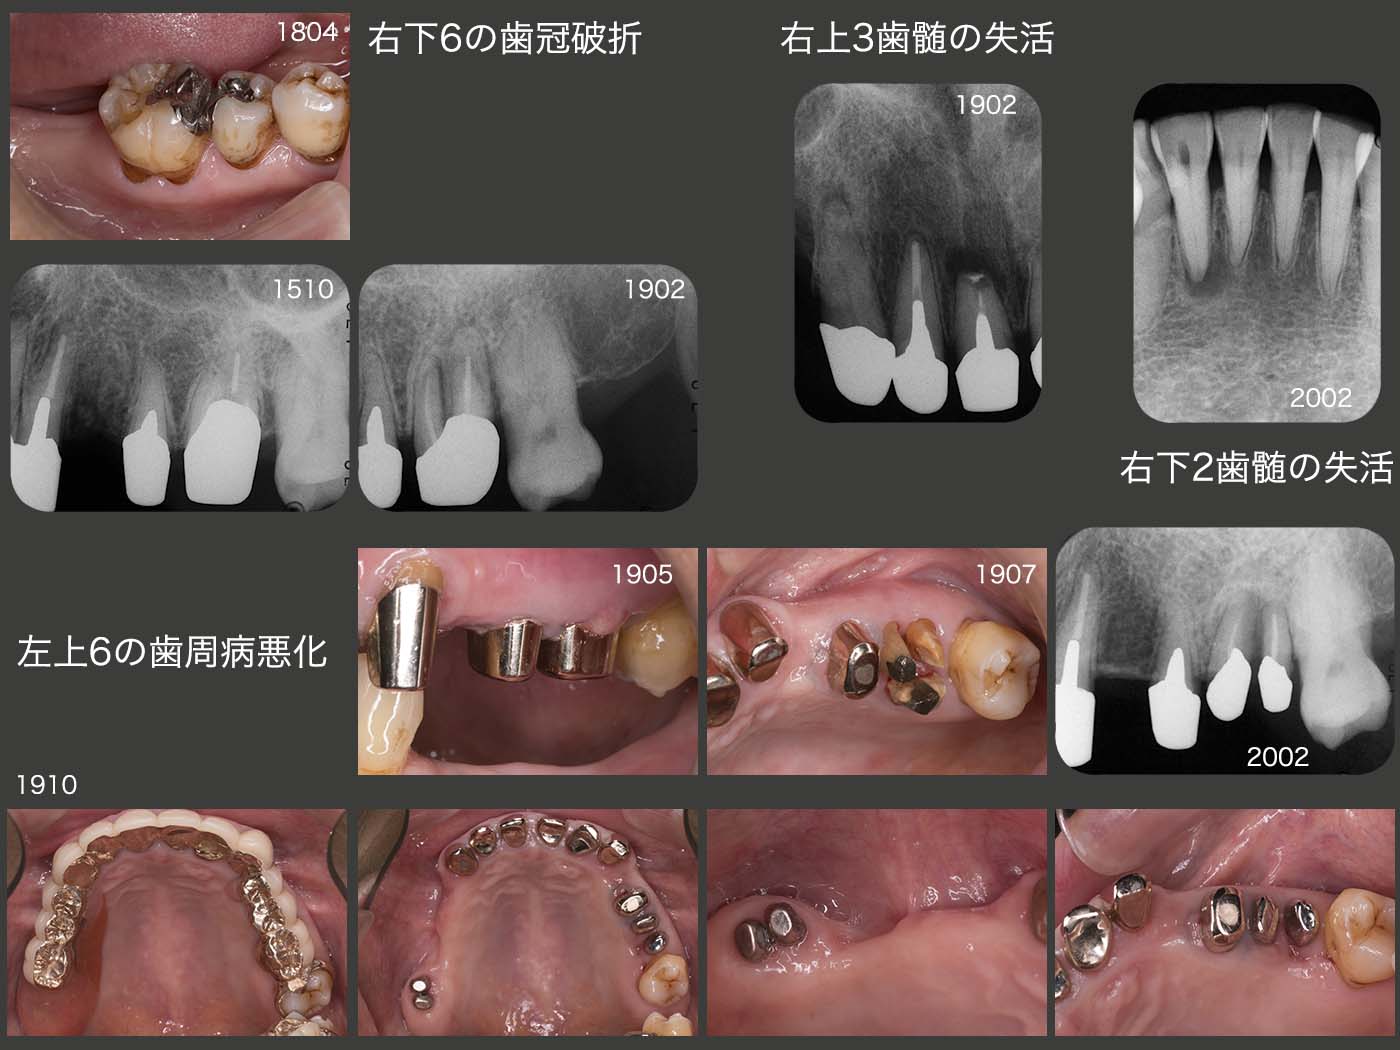

2018年4月,右下6に歯冠破折がみられた.対合歯がなくなってもまだここで咀嚼しているのかもしれない.また19年2月に,右上3の歯髄が失活してしまった.形成量が多過ぎたと言われればそのとおりであるが,力も関与しているのではないかと勘ぐってしまう.同年5月,左上6に歯肉膿瘍が生じた.内冠を除去し,歯周ポケットが10mm以上になってしまった口蓋根を抜去した後,10月,頰側2根にそれぞれ根面板を装着した.移植の失敗した右上6部の顎堤はやせ細り,心が痛む.20年2月,右下2の歯髄が失活した.16年3月に行ったコンポジットレジン充塡が歯髄に近接していたことが理由であろう.